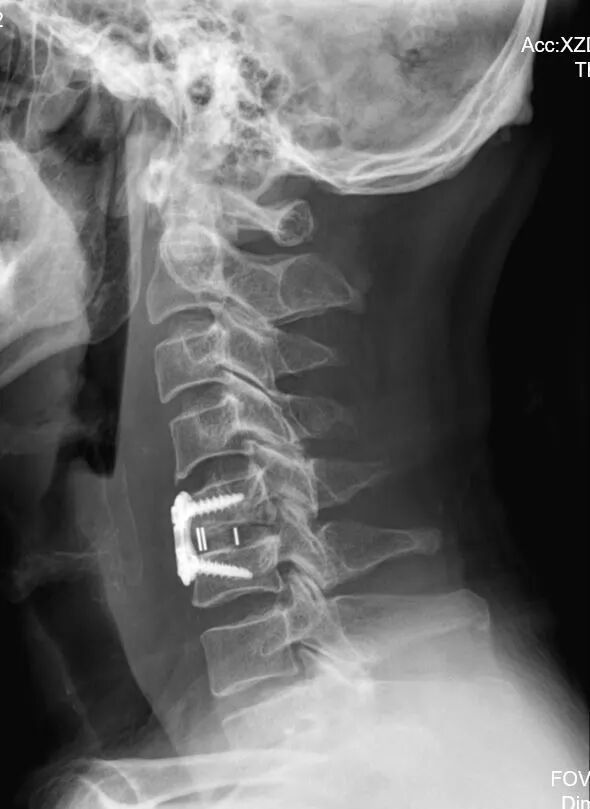

颈前路髓核摘除椎管减压、椎间植骨融合内固定术

仅耗时2小时,出血量20ml

顺利完成手术,主打一个微创高效

术后恢复更是“开挂”

第三天,李先生就能下床正常行走